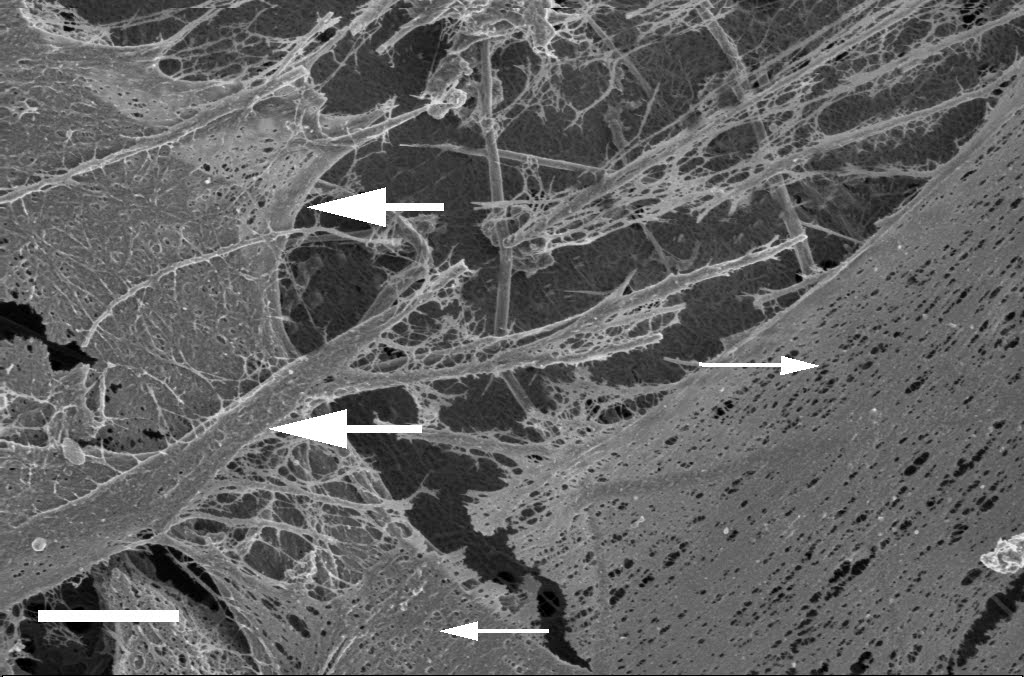

The Micrograph shown here, shows the ultrastructure during stroke. Dense matted deposites (arrows) are formed in the body and this may block blood vessels.

The ultrastructure of stroke

Stroke is one of the leading causes of death world wide. There are two main devisions of stroke, namely haemorrhagic stroke, caused mainly by bleeding in the brain; and thrombotic stroke. This is caused by a thrombus or blood clot. This may develop due to a changed coagulation profile, resulting in a matted and dense fibrin clot. This is visible under an electron microscope when creating a clot, by taking citrate blood from an individual, and mixing it with thrombin. This thrombin addition causes a cascade of biochemical pathways to be activated, just as what typically will happen in the human body. A changed coagulation profile, as seen during stroke, may therefore be detected using a simple and cheap morphological screening tool. Follow-up investigations, after a stroke, can also be done to determine the success of the treatement.